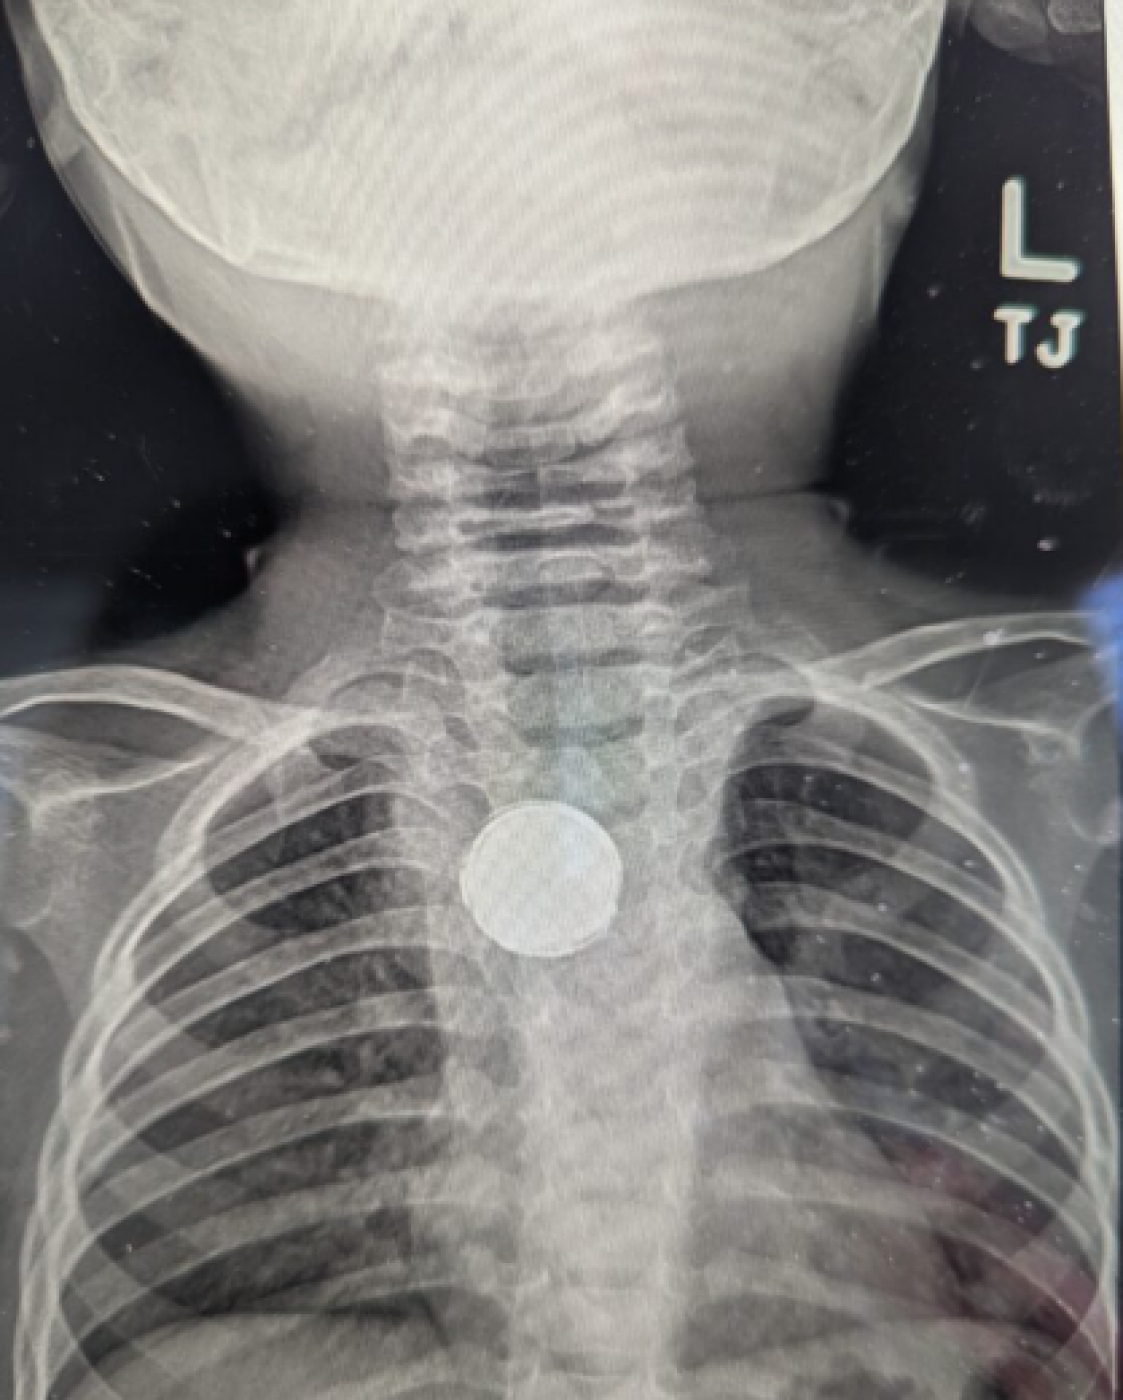

Nakon što su posetili drugog pedijatra, Lukeje poslat na rendgen grudnog koša, što je izazvalo zaprepašćenje medicinskog osoblja. Lekari su pitali Eriku da li je Luk možda progutao novčić ili nosio ogrlicu sa dugmetom, na šta je ona odgovorila negativno.

Printscreen Courtesy Intermountain Primary Children's Hospital ❮❯

Dečak je hitno prebačen u bolnicu, gde su doktori ustanovili da je mališan progutao litijumsku baterija koja je bila zaglavljena u njegovom jednjaku punih pet nedelja. Iako je okrugla baterija oštetila tkivo jednjaka, bila je umotana u električnu traku, što je verovatno spaslo Lukov život. Naime, kako navode lekari, ove baterije počinju da korodiraju već posle dva sata, čime bi mališan verovatno imao stravične posledice.